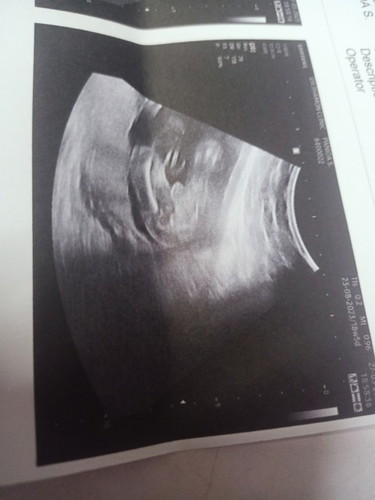

แบบนี้ มีจู๋ใช่ไหมคะ

น่าจะใช่แล้วค่า

หม่่ามี๊ of 2 ช่างถาม เจ้าชาย